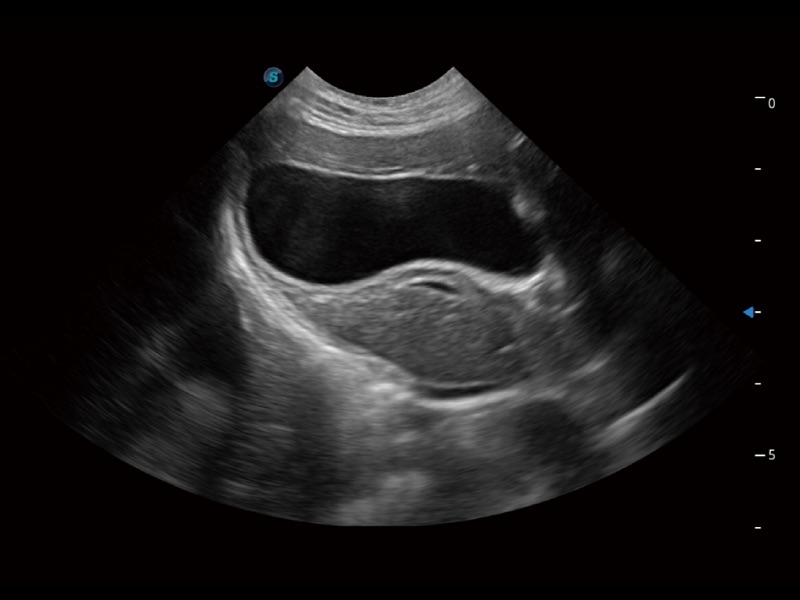

优异的基础图像

ProPet 70 全新的动物超声智能软件和丰富的探头群,为动物医生提供了高清晰度和精细分辨率的图像,无论在宠物、马科、畜牧还是实验室动物等应用中都可以轻松应对,为您的日常工作带来满意的体验。

(猫)胆囊

(犬)四腔心